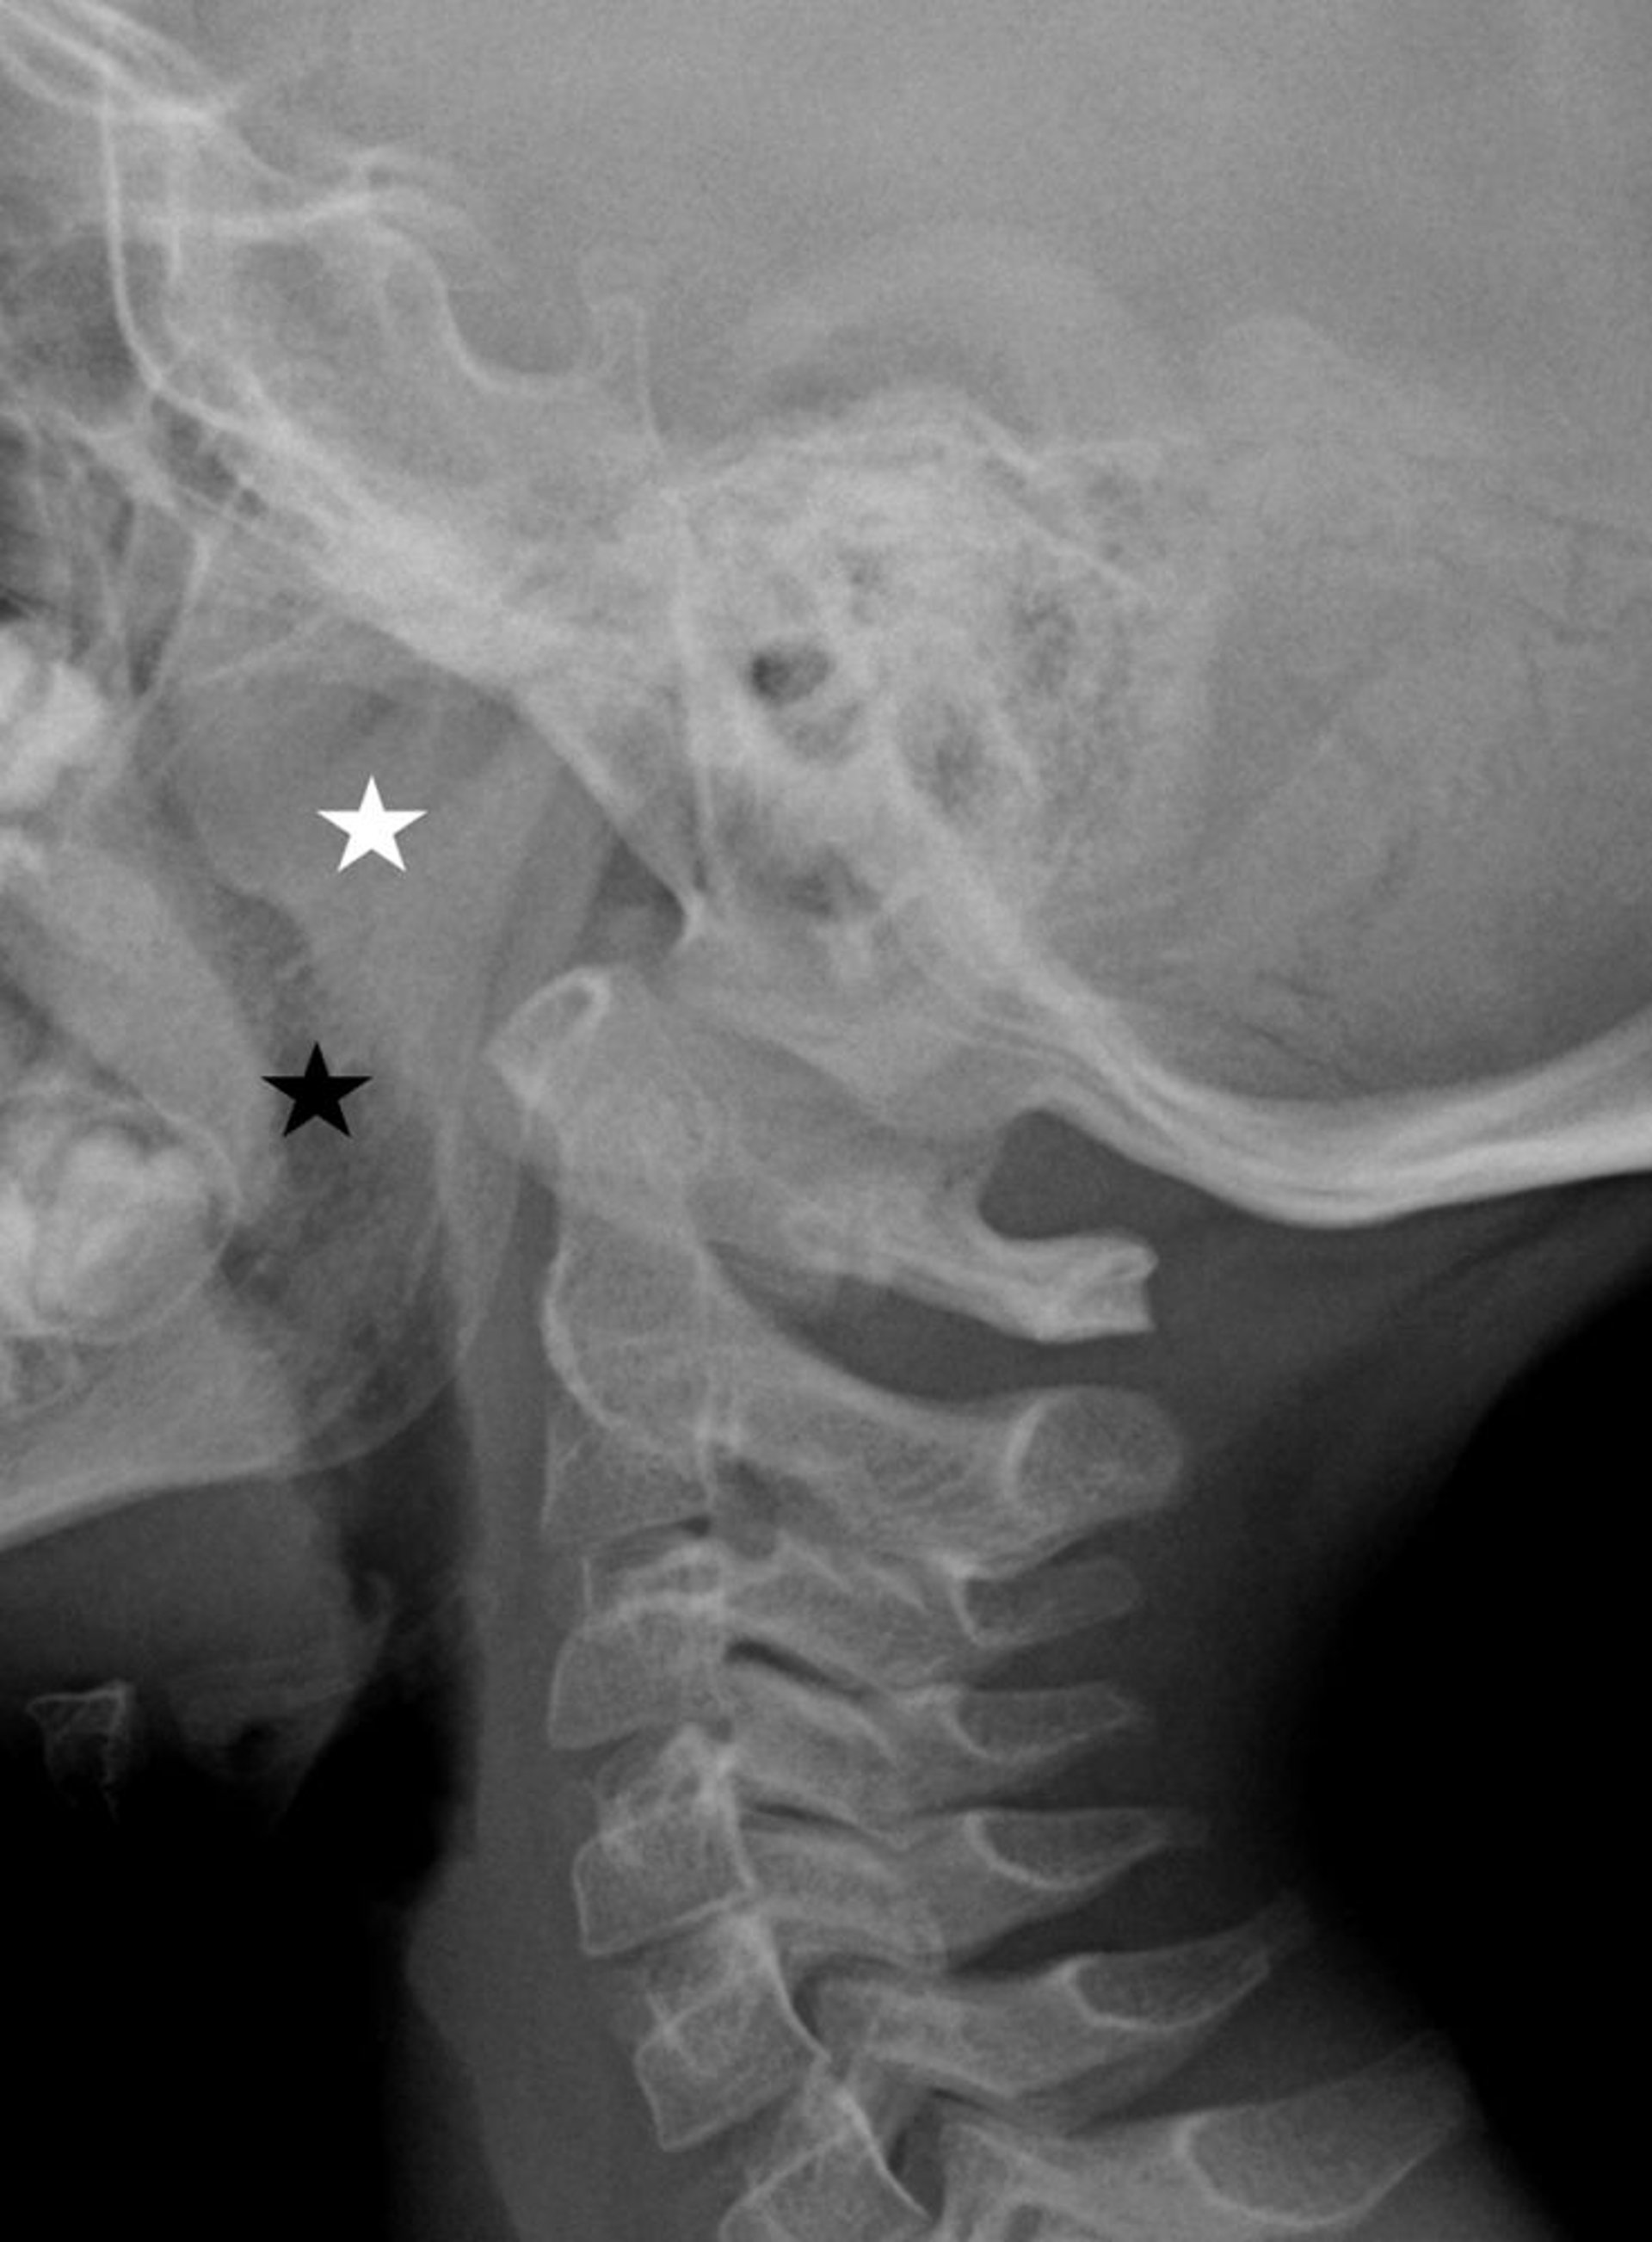

Adénoïdes (végétations) augmentées de volume (radiographie)

Cette radiographie montre de grandes végétations adénoïdes (étoile blanche) provoquant un rétrécissement des voies respiratoires (étoile noire).